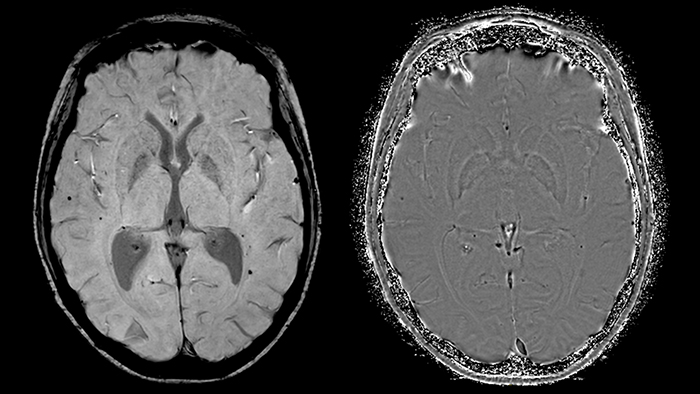

Умножение этой маски на магнитудное изображение никак не повлияет на области с положительной накопленной фазой, но повысит контрастность областей с повышенным содержанием парамагнитного железа. Конечный результат последовательности SWIp – SWI- и отфильтрованное фазовое изображение (рис. 6), обладающие уникальным контрастом, при этом первое отражает как локальные изменения магнитной восприимчивости тканей, так и значение амплитуды МР-сигнала. Таким образом, принципиальное преимущество метода SWIp по отношению к T2*-взвешенным изображениям - использование фазовых данных для повышения первоначального контраста магнитудных изображений. Это обуславливает более высокую диагностическую ценность этой методики по сравнению с T2* последовательностями [9].

Как правило, для просмотра этих изображений применяется метод проекции минимальной интенсивности (Minimum intensity projection, mIP). Используется информация из срезов в определенном объеме толщиной до 10 мм [10], причем для построения mIP из каждого среза выбираются наименее интенсивные области. Такой способ отображения SWI изображений упрощает визуализацию гипоинтенсивных структур, таких как парамагнитные вены.